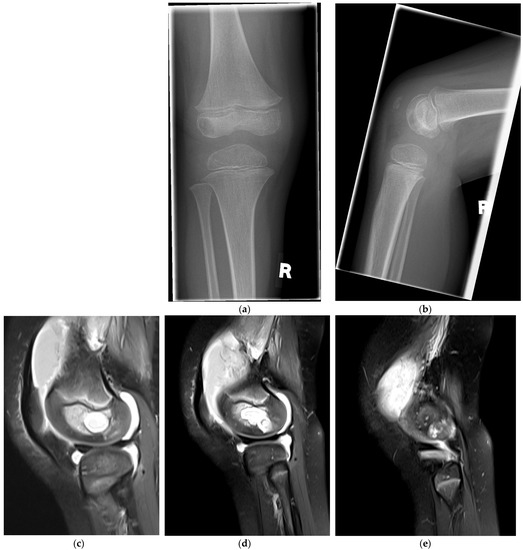

Surgical Management of an Osteomyelitis Associated Subchondral Bone Defect in the Pediatric Knee Based on Arthroscopy, “Ossoscopy” and Bone Grafting—A Case Report

2. Case Presentation